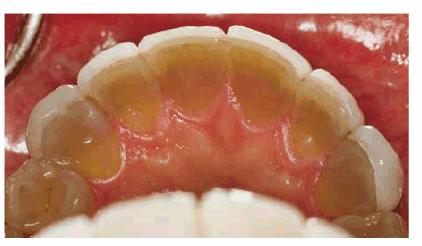

TETRACYCLINE STAINING

Tetracycline is considered one of the most difficult tooth stains to remove.

In-office bleaching is a possible treatment method but generally is

contraindicated due to the number of treatments required and the concurrent

high fee and patient discomfort. With the advent of at-home bleaching, these

tetracycline stains can be managed more easily.49,51,60 Treatment

times may vary from 2 months to 1 year (Figures 16-28A 16-28B 16-28C 16-29A 16-29B 16-30A 16-30B 16-31A, and 16-31B). Patients are seen monthly to

replenish solutions and evaluate for continuing color change. Patients should

agree to a minimum of 2 months of nightly treatment before deciding to proceed

to more aggressive treatment. Fees are generally the cost of a monthly office

recall visit and additional material. Once lightening is observed, patients

should continue treatment until a month has passed with no obvious color

change. Dark tetracycline stains located in the gingival third of the tooth or

dark blue or gray stains have the least favorable prognosis. However, even in

these situations, there can be some improvement. This improvement may be

sufficient for the patient's esthetic demands. However, compliance by the

patient is necessary for success. Patients with tetracycline staining often

Figure 16-32A: Extent of the discoloration is evident from the lingual view of the maxillary teeth and the unrestored mandibular teeth.